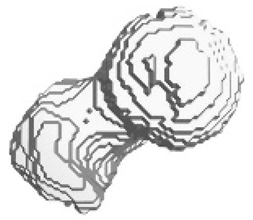

| Isometric View of the Left Femur | Ground Truth and Predicted Results of the Left Femur under Dataset Category F-I | |||||

|  | Front | Left | Rear | Right | Top | Bottom |

| Ground Truth |  |  |  |  |  |  |

| Prediction |  |  |  |  |  |  |

| SAM | 0.211 | 0.214 | 0.209 | 0.223 | 0.243 | 0.257 |

| SSIM | 0.433 | 0.454 | 0.501 | 0.532 | 0.502 | 0.544 |